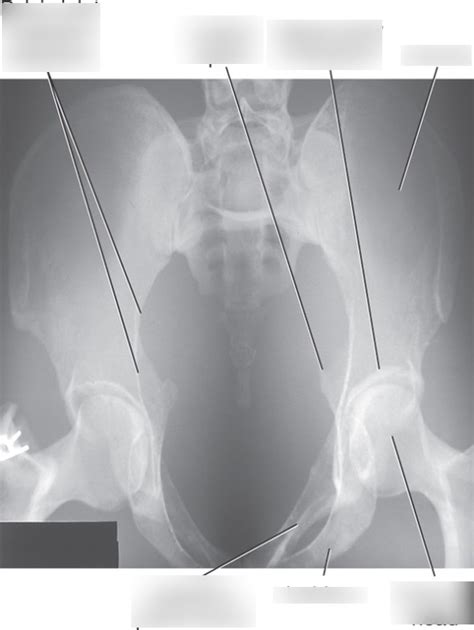

Image Evaluation and Anatomy

Key Anatomical Structures to Identify:

• Sacroiliac (SI) Joints: These joints connect the sacrum to the iliac bones. On the AP Axial view, you should be able to clearly visualize the SI joints and assess their alignment and joint space.

• Symphysis Pubis: This is the joint where the two pubic bones meet in the front of the pelvis. Look for any widening or displacement of the symphysis pubis, which could indicate a pelvic fracture or instability.

• Pelvic Inlet: This is the opening into the true pelvis. The AP Axial view is designed to provide a clear view of the pelvic inlet, allowing you to assess its shape and symmetry. Any distortion or asymmetry could suggest a fracture or dislocation.

• Iliac Crests, Ischial Spines, and Pubic Rami: These bony landmarks should be clearly visible and free from any obvious fractures or deformities.

• Sacrum and Coccyx: Although the primary focus is on the pelvic ring, it’s also important to assess the sacrum and coccyx for any abnormalities.

• Rotation: Check for rotation by assessing the symmetry of the obturator foramina and the iliac wings. If one obturator foramen appears larger than the other, or if one iliac wing is more prominent, the pelvis is likely rotated.

• Collimation: Ensure that the collimation includes the entire pelvis, from the iliac crests to the proximal femurs. Cutting off any of these structures could result in a missed diagnosis.

• Exposure: The image should have adequate density and contrast to clearly visualize the bony structures of the pelvis. Overexposure (too dark) can obscure subtle fractures, while underexposure (too light) can make it difficult to assess the soft tissues.